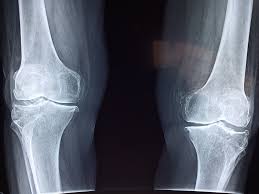

Can damaged cartilage be fixed? Glucosamine glucosamine is found naturally in the body, though it can also be obtained from shrimp, crab, and lobster. When damaged in the joints, it can lead to pain, inflammation, limited range of motion and stiffness that can eventually progress to osteoarthritis (oa)the most common type of arthritis. See full list on arrowheadhealth.com As stated throughout the article, most people will not be able to fully treat their osteoarthritis through food alone. Jul 27, 2015 · foods rich in vitamin a stimulate cartilage regeneration on the hip and knee. Jul 01, 2018 · you could definitely use these foods and exercise to repair the damaged cartilage naturally. Nutreance.com has been visited by 10k+ users in the past month

Hyaluronic acid can be produced naturally in your body but the ability decreases as you age. Beans, peas, and peanuts are all considered legumes, which means that you have numerous options to sneak more of them into your diet. Clinically proven to help grow joint cartilage in 2 weeks. How do you rebuild joint cartilage? For optimal joint function, it is important to beat inflammation wherever possibleinflammation is the primary source of collagen and, by extension, cartilage breakdown.

Hyaluronic acid can be produced naturally in your body but the ability decreases as you age. Vitamin k is essential for bone and joint health. See full list on arrowheadhealth.com See full list on arrowheadhealth.com Find knee cartilage injury help here. More images for how to build cartilage in knee naturally » Dark green and leafy vegetables. Remember when your mom used to force you to eat those green leafy vegetables? Glucosamine glucosamine is found naturally in the body, though it can also be obtained from shrimp, crab, and lobster. Here is a list of foods that help rebuild cartilage. Nutreance.com has been visited by 10k+ users in the past month Luckily, it is found in many foods, being especially abundant brussels sprouts. Hence eating foods rich in vitamin c and hyaluronic acid can help to boost collagen production in your body more efficiently hence knee cartilage will be benefited.